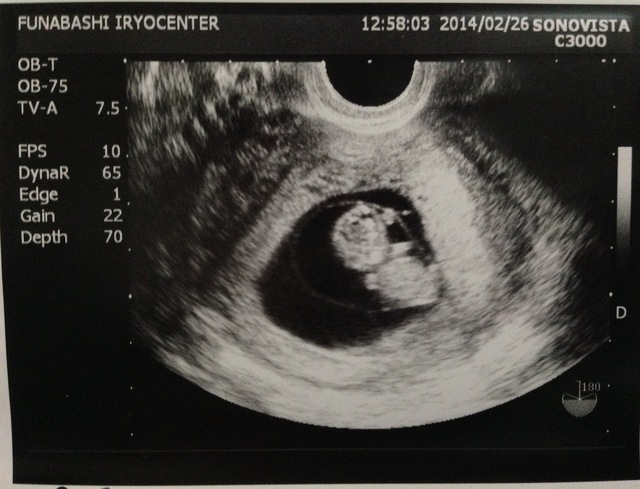

9週0日(9w0d・性別不明・双子)|みーやま さん(27歳)

エコー写真撮影時のエピソード:

なかなか授からず、3年目にして授かり毎回検診でちゃんと育っているか不安でした。この9wの時、双子が発覚!!驚きとうれしさと不安にもなりました。

けど、旦那も親も喜んでくれて、今まで不妊治療を頑張ってきて本当に良かったと思いました。つわりも妊娠後期も体調がよくなく、管理入院になりましたが、無事元気に生まれてくれて、今本当に幸せです。